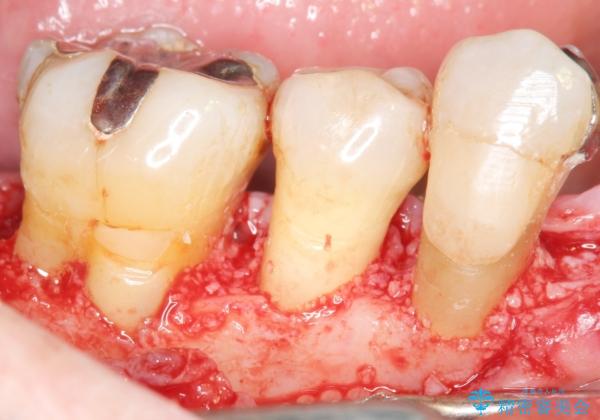

骨吸収の進行している右下臼歯部に、再生療法(骨を増やす手術))を行いました。

再生療法から1年後、リエントリー手術により骨の再生を確認し、骨外科処置(骨を平らにして歯周ポケットの根本的な改善を図る処置)を行いました。

再生療法と骨外科処置により、歯周ポケットは全周2mm以下となりました。